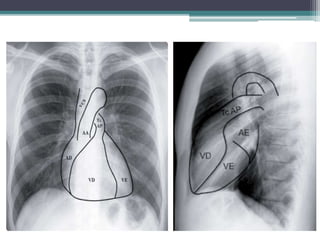

Avaliação diagnóstica

• Exames de imageamento

▫ Radiografia de tórax;

▫ Tomografia computadorizada;

▫ Imageamento por ressonância magnética;